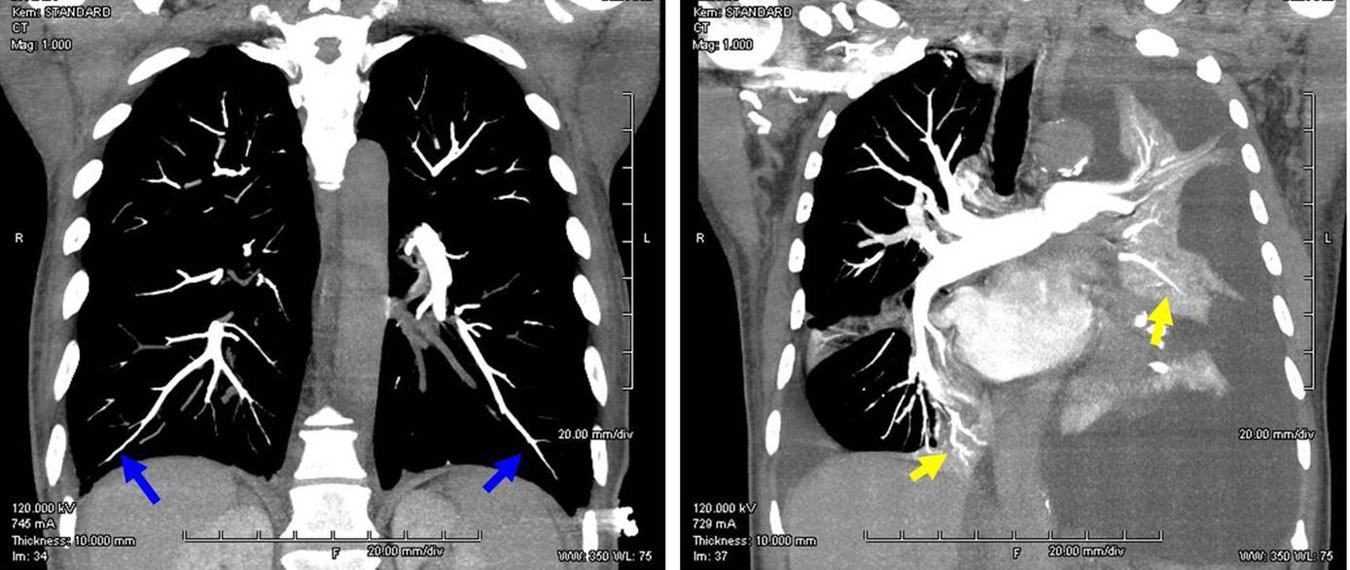

image